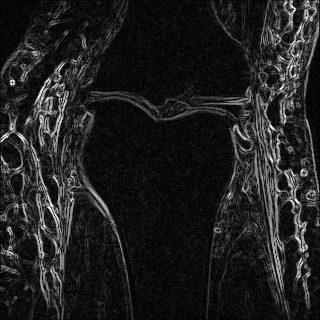

Edge preserving has always been a crucial concern in the design of reconstruction models. To improve the quality of reconstructed images and preserve image edges, some works suggested introducing edge priors in the original restoration problem to preserve image edges [4, 34]. However, they will suffer from complicated algorithm design and time-consuming training processes. Recently, some more efficient methods have been proposed to use edge maps as external guidance for image restoration. For example, Yang et al. [48] used off-the-shelf edge detectors to extract image edges from the degraded images. Fang et al. [12] predicted image edges by constructing an edge reconstruction network. Huang et al. [18] designed a novel dual discriminator GAN framework for solving fast multi-channel MRI, in which one GAN network is built for edge information enhancement. Inspired by these methods, we also consider introducing image edge prior as external guidance to MRI reconstruction since 1) image edges are prominent and distinguishable features in MRI (see Fig. 1), which can serve as a good guide to the model to recover high-frequency details; 2) the ground truth edges can be easily fetched via ordinary edge extraction operators, like Canny, Sobel, and Prewitt, which means that the edge maps can be learned in a data-driven manner. However, how to effectively utilize image edge priors to guide image reconstruction still remains a challenge. In some methods, edge information was simply concatenated with the input image and passed to the next stages. Though this is a simple way to utilize the edge priors, it may not give full play to the guiding role of the edge priors. Therefore, in this work, we want to explore a more efficient and effective mechanism to fully take advantage of image edge priors.

(a)

(b)

(c)

fastMRI is a large-scale MR dataset jointly established by Facebook AI Research and NYU Langone Health. It provides both knee and brain datasets for evaluation. In our work, we use the multi-coil knee dataset, which was acquired on three clinical 3T systems or one clinical 1.5T system using a 15-channel knee coil array. The dataset includes data from two pulse sequences, yielding coronal proton-density weighting with (PDFS) and without (PD) fat suppression. As is shown in Fig. 1, PD images usually contain more structural and prominent edge features than PDFS images, which suggests that it is more challenging to use edge guidance on PDFS datasets. Therefore, we explore the effectiveness of EAMRI on these two modalities. Following [13], for both PD and PDFS knee datasets, we separately filter out 227 volumes (8332 slices) for training and 24 volumes (1665 slices) for testing. The dataset is centrally cropped to .